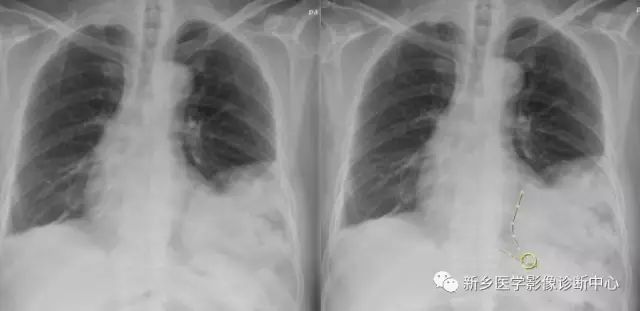

五、创伤性膈疝

外伤时,导致膈肌破裂口较大时,腹内脏器可嵌入胸腔,形成创伤性膈疝。